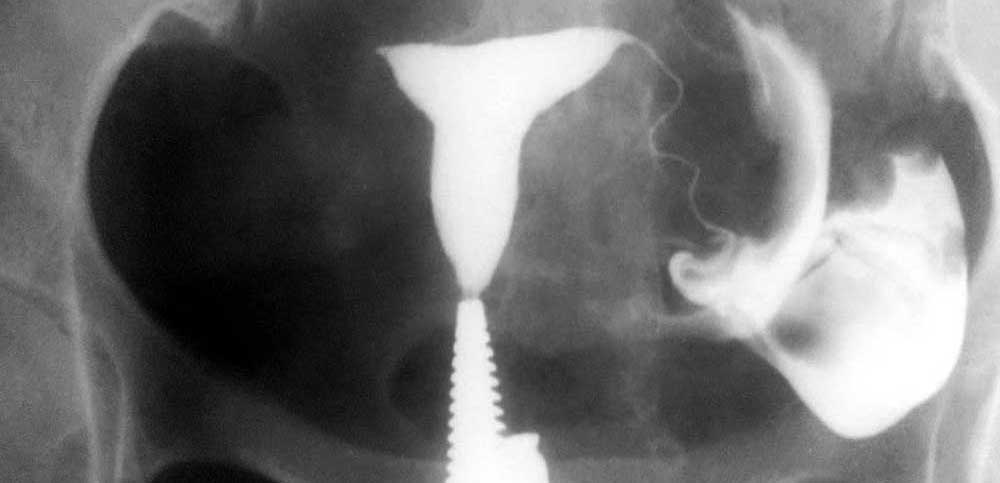

بیمار در وضعیت زنان (به پشت خوابیده، زانوهای خم شده و از هم باز)، زیر دستگاه اشعه ایکس قرار می گیرد. پزشک یک اسپکولوم را وارد واژن میکند، سپس یک کانولا را در دهانه رحم قرار میدهد که از طریق آن یک ماده حاجب تزریق میکند. این به داخل رحم و لوله های فالوپ گسترش می یابد. اشعه ایکس برای مشاهده پیشرفت خوب محصول و تجسم اندام ها گرفته می شود.

هیستروسالپنگوگرافی توسط رادیولوژیست انجام می شود. معاینه بدون بیهوشی انجام می شود. بیمار در موقعیت "زنان و زایمان" مستقر می شود. پزشک اسپکولوم را قرار می دهد، دهانه رحم را ضد عفونی می کند و سپس یک پروب را با روش طبیعی وارد رحم می کند. او به تدریج ماده حاجب را تزریق می کند. به طور معمول، ماده حاجب به تدریج رحم و لوله های فالوپ را کدر می کند تا زمانی که به حفره صفاقی منتقل شود.

چندین عکس رنگی رحم قبل، حین و بعد از تزریق محصول گرفته می شود و این در موقعیت های مختلف:

اشعه ایکس بدون آماده سازی (جستجو برای کلسیفیکاسیون لگن)؛

اشعه ایکس پر شدن ضعیف (پولیپ ها یا فیبروم های زیر مخاطی را برجسته می کند).

اشعه ایکس پر شدن لوله (ارزیابی وضعیت مخاط لوله).

عکس پروفایل (ارزیابی موقعیت رحم و مسیر لوله های فالوپ)؛

اشعه ایکس دیررس (بررسی گردش خون صفاقی، جستجو برای چسبندگی لگن).

در اصل، HSG یک ارزیابی رادیوگرافی از حفره رحم و لوله های فالوپ با استفاده از فلوروسکوپی سرپایی بلادرنگ با تزریق ماده حاجب رادیویی مات از طریق کانال دهانه رحم را نشان می دهد. کانال دهانه رحم، کانتور حفره رحم و لومینای رحم و لوله شامل بخش های قرنیه، ایستمی و آمپولری و تعیین